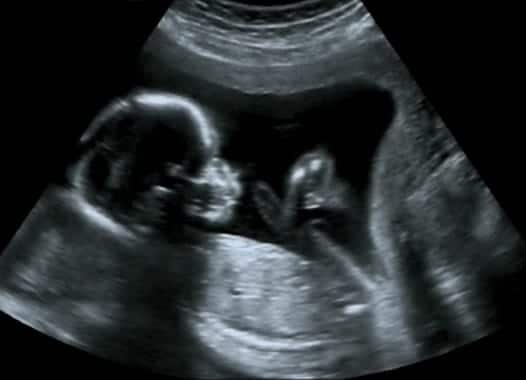

בדיקות אולטרא סאונד מבוצעות מספר פעמים לאורך תקופת ההריון, ותפקידן לבדוק את מצב העובר ואת התפתחותו התקינה. כאשר מומים ולקויות שונים אינם מאובחנים בבדיקות האולטרא סאונד, הדבר יכול להוות עילה לתביעה.

כאשר הריון עובר בצורה חלקה, מקובל לערוך בדיקות אולטרא סאונד אחת לשלושה חודשים. בבדיקה הראשונה מתבצעת סקירת מערכות של העובר, במטרה לאתר מומים וליקויים שהתפתחו ברחם. מדובר בבדיקה פולשנית, ולכן היא מבוצעת על ידי רופא נשים המתמחה בתחום.

הבדיקה השנייה היא חיצונית (על פני הבטן), ובבדיקה זו נסרקים עמוד השדרה, הלב, המוח ואיברים פנימיים נוספים. בדיקות האולטרא סאונד אינן כוללות סריקה של כל איברי ומערכות הגוף, ולכן החוק מחייב את הרופא ליידע כל אישה הרה על האפשרות לבצע בדיקה מורחבת הכרוכה בתשלום נוסף.

כאשר נולד תינוק בעל מומים, מתעורר חשד למקרה של התרשלות בבדיקות האולטרא סאונד. על מנת לבדוק חשד זה נעשית סריקה של הבדיקות שהתבצעו במהלך ההריון, ובה נבדקות שאלות כגון: האם הבדיקה התבצעה בצורה נכונה? האם ניתן היה לאתר את המום בתוצאות הבדיקה? ושאלות דומות נוספות.